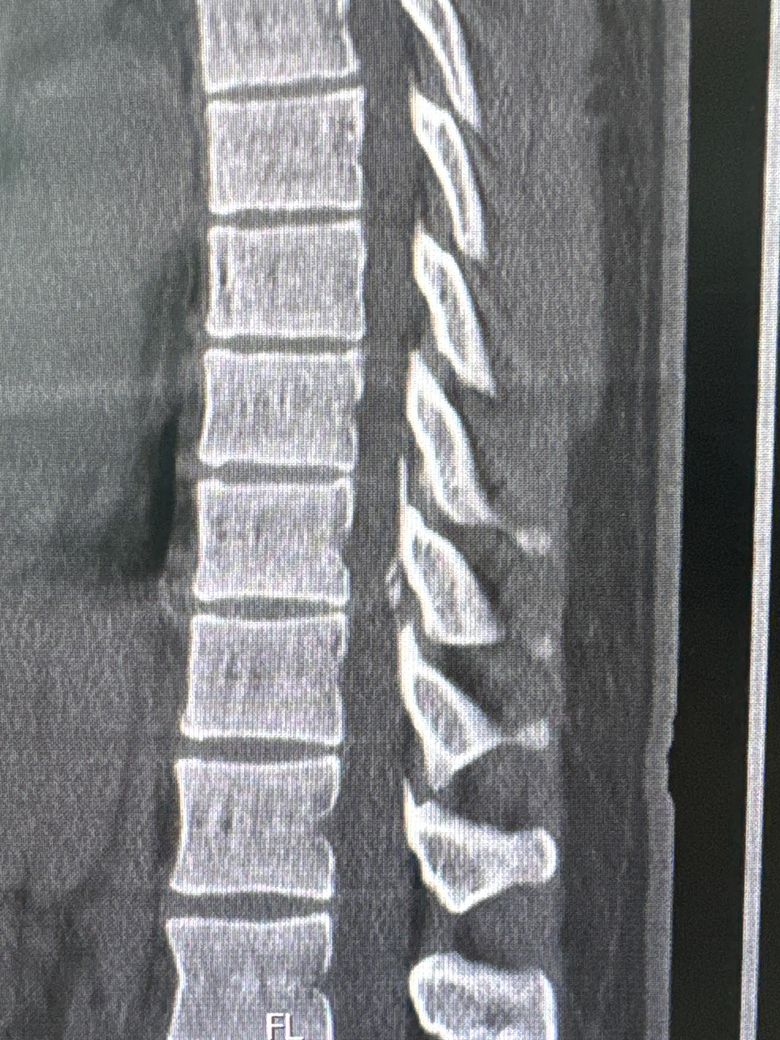

T10/T11쪽인데 신경외과 전문의가 수술할 정도는 아니고 약이랑 블럭주사 정도로 경과를 지켜보자 하셔서 그런데 혹시 대학병원에는 석회를 녹이는 주사나 다른 치료방법이 있을까요? 등은 주기적으로 3~4개월에 아픈데 가끔 등을 삐끗하면 바로 아픕니다ㅜㅜ 9/27일에 MBB맞고 10/23일에 또 맞았는데 오늘이 너무 아팠습니다. 치료방법과 재발 가능성을 낮추는 방법이 있을까요?

• 1번 째 사진